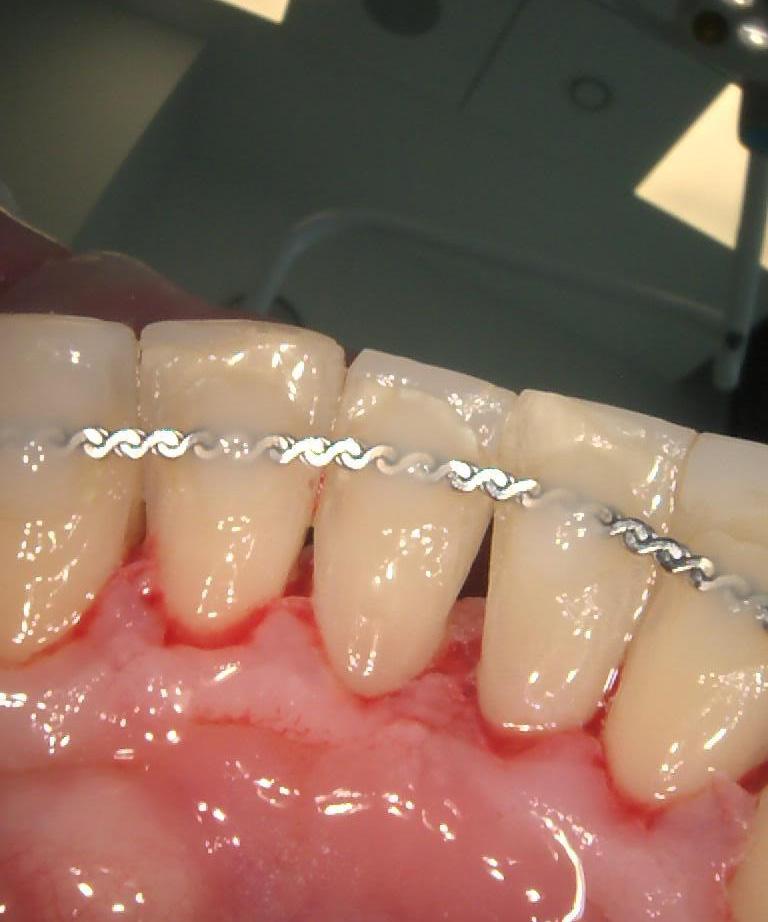

Podczas gdy w dolnym łuku dr Michał Mokijewski przeprowadzał zabiegi regeneracyjne i implantacje, zajęłyśmy się leczeniem łuku górnego.

Zgodnie z zasadą, że prace protetyczne powinny być oparte na zdrowych i solidnych fundamentach, zaczęłyśmy od podstaw – wymiana nieszczelnych wypełnień, powtórne leczenia kanałowe.

Praca została zwieńczona odbudową zębów koronami cyrkonowymi. Brakujący ząb, którego nie można było uzupełnić implantem z powodu za małej ilości miejsca, odtworzono za pomocą cyrkonowego mostu.

Zgodnie z życzeniem Pacjentki poprawiony został kolor i kształt zębów. Kamuflaż protetyczny umożliwił także skorygowanie asymetrii.

Dzięki profesjonalizmowi naszych lekarzy, Pacjentka ma teraz zdrowy, piękny uśmiech!